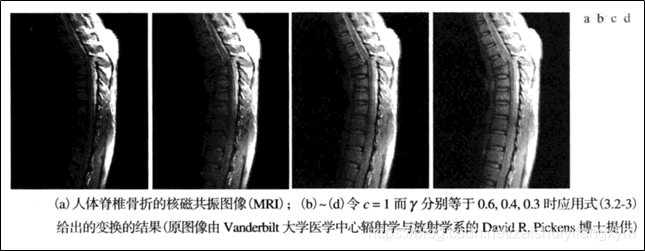

下图所示为图像伽马变换的例子: